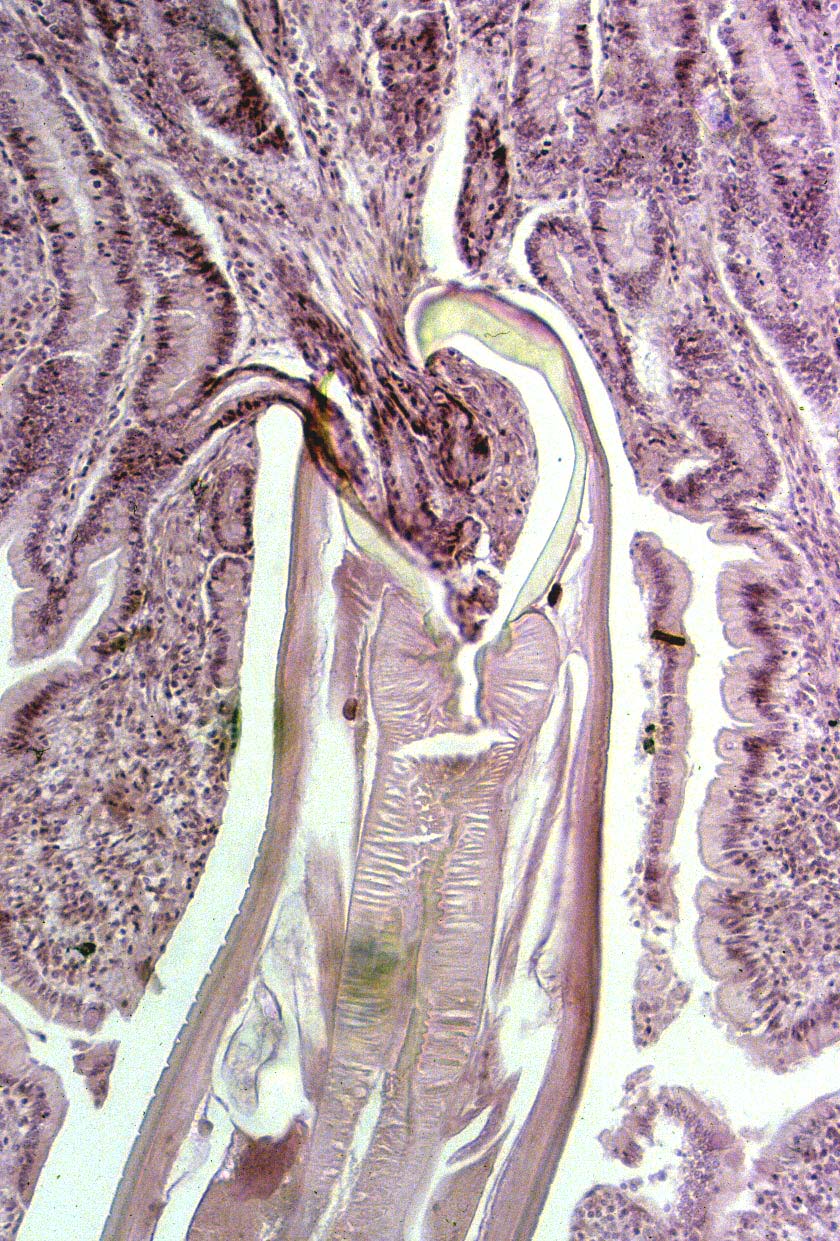

anchilostoma

Scienziati australiani stanno sviluppando una nuova terapia contro i disturbi autoimmuni come la celiachia, un’intolleranza permanente al glutine presente nei cereali, ma il trattamento puo’ incontrare una certa riluttanza, poiche’ consiste nell’infettarsi con vermi parassiti. L’equipe del prof. James Daveson, dell’ospedale Princess Alexandra di Brisbane, ha contagiato 20 volontari che soffrono di celiachia con il parassita intestinale detto anchilostoma, le cui larve penetrano per via orale o cutanea nell’uomo e si attaccano alla parete intestinale. Il parassita, che sta scomparendo dalle societa’ occidentali a causa della forte enfasi sull’igiene, ha dimostrato di poter produrre una maggiore tolleranza a cibi come pane e pasta.

”I pazienti che hanno ospitato il parassita hanno tollerato meglio il glutine, con migliori risultati nei test rispetto ai soggetti del gruppo di controllo; hanno accusato minori infiammazioni e meno danni alla parete intestinale”, ha spiegato Daveson in una relazione ad un convegno della Settimana della gastroenterologia, in corso a Sydney. Una rigorosa dieta senza glutine e’ finora l’unica terapia che garantisce al celiaco un buono stato di salute. Altrimenti il sistema immunitario lo combatte come un invasore nemico’ e gli anticorpi attaccano le pareti intestinali, causando problemi che vanno dalla diarrea cronica al cancro. Lo studioso ha spiegato che la ricerca si e’ basata sulla teoria secondo cui il sistema immunitario ha bisogno di essere esposto ad organismi estranei, per funzionare bene. Diversi studi hanno mostrato un legame fra gli alti standard di igiene ed il numero crescente di malattie autoimmuni. ”L’uomo si e’ evoluto insieme con essi, eppure abbiamo sterilizzato il nostro mondo cosi’ bene che non abbiamo piu’ vermi nel nostro intestino. Alcuni esperti ritengono che questa sia una delle ragioni per cui assistiamo ad una crescita allarmante di disturbi auto immuni come la celiachia, ma anche l’asma e la sclerosi multipla”, ha aggiunto. I vermi usati nella sperimentazione convivono solo con l’uomo, e non sono facilmente trasmissibili da persona a persona. Dopo la sperimentazione di 21 giorni, ai volontari e’ stata offerto un trattamento per liberasi dei parassiti, ma tutti hanno scelto di continuare ad ospitarli. (ANSA).